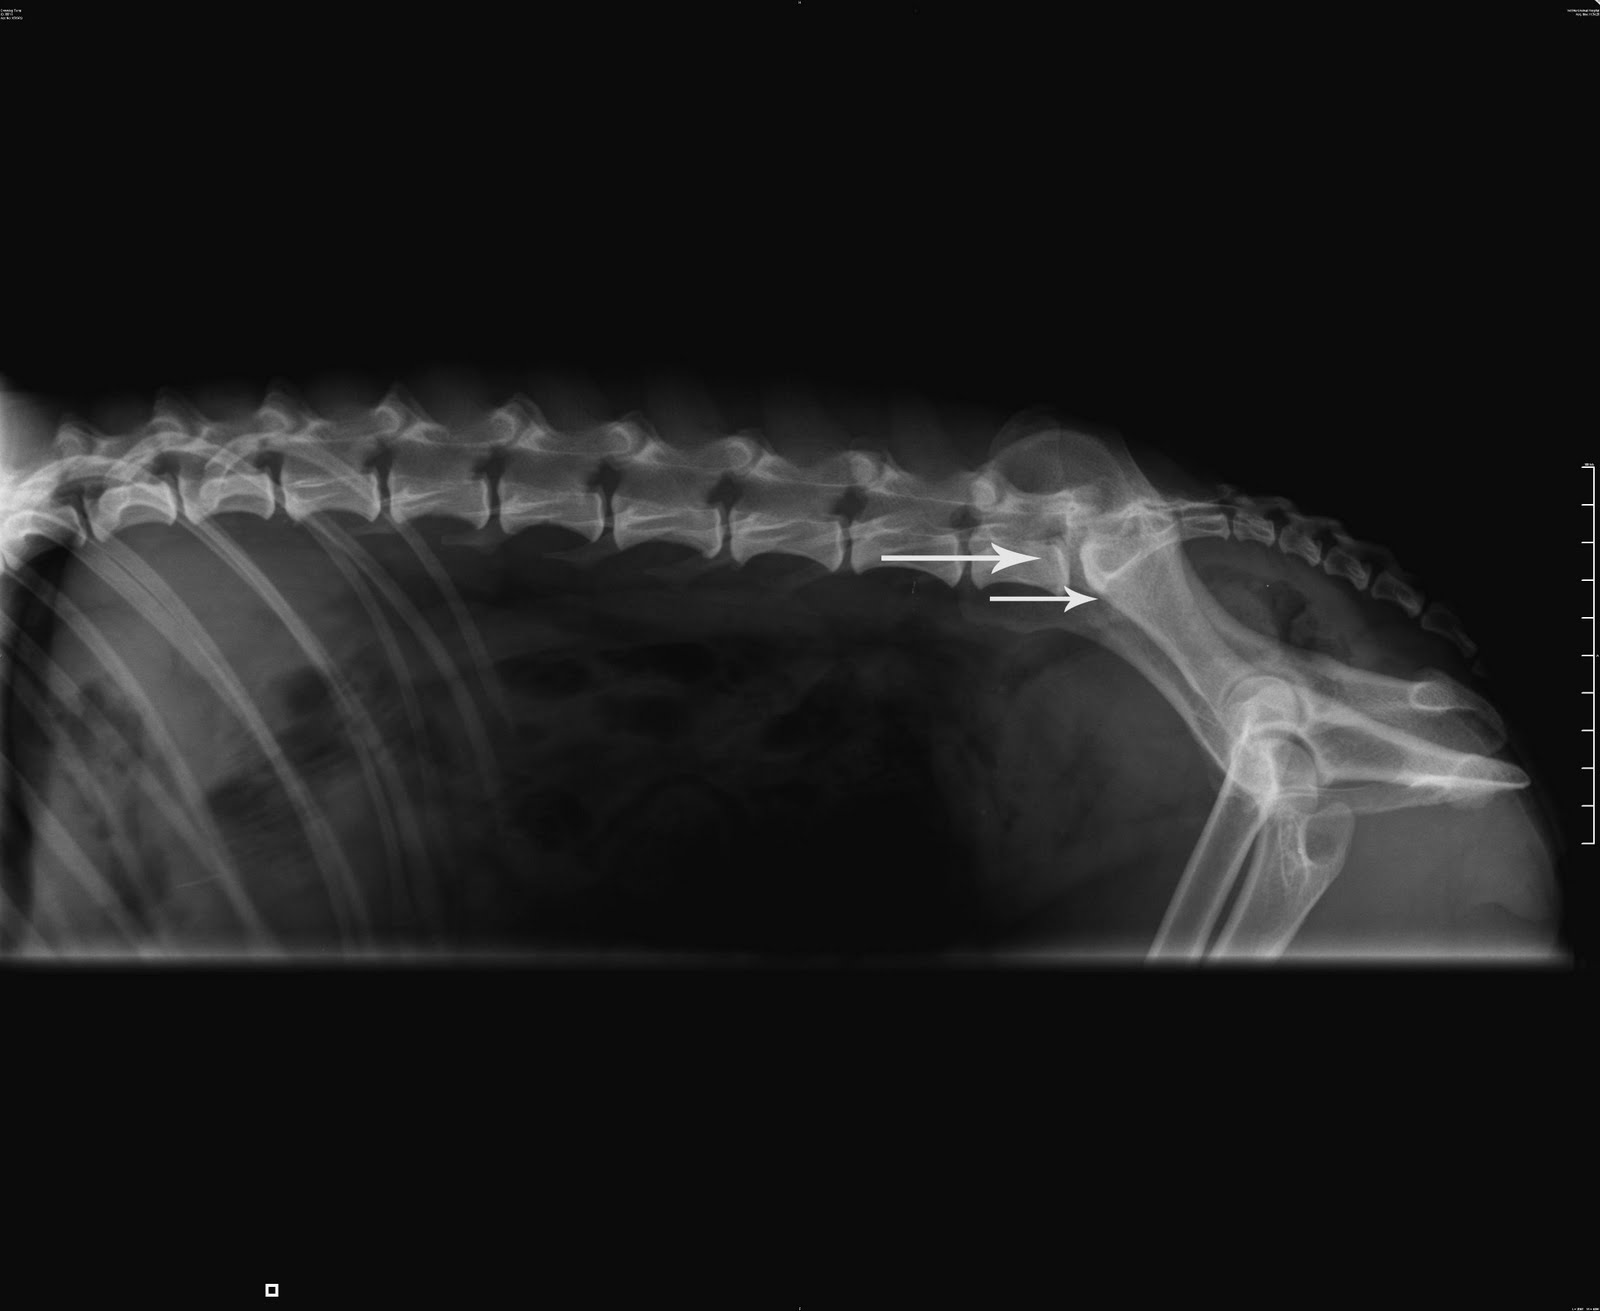

Излом хвоста

Излом хвоста 112 фото